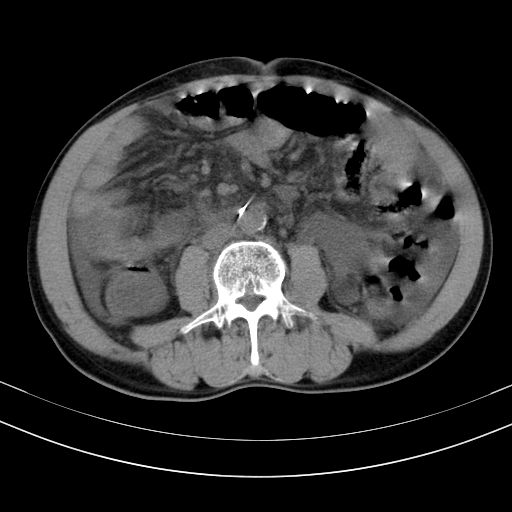

以下是引用随光逐影在2010-2-28 10:23:00的发言:[br]1)考虑肝癌;建议行ct增强扫描检查。2)肝硬化,脾大,腹水。3)慢性胆囊炎。

以下是引用dyqct在2010-2-28 16:44:00的发言:[br][quote]以下是引用随光逐影在2010-2-28 10:23:00的发言:[br]1)考虑肝癌;建议行ct增强扫描检查。2)肝硬化,脾大,腹水。3)慢性胆囊炎。